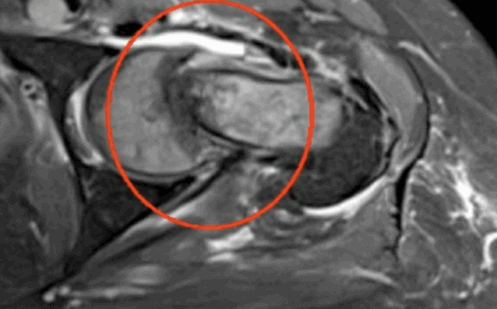

Импиджмент синдром на МР-фото

Магнитно-резонансное сканирование проводят для диагностики ряда патологических состояний. Что показывает МРТ тазобедренного сустава? На снимках визуализируются:

К механическому конфликту между бедренной головкой/шейкой и краем вертлужной впадины приводят одно- или двусторонние дефекты костей врожденного или приобретенного генеза. Видоизмененные компоненты сочленения вызывают дисфункцию конечности за счет соударения во время движения. Патологическое трение костей способствует разрастанию остеофитов на фоне постоянной травматизации вертлужной губы. Если своевременно не диагностировать заболевание и не начать лечение, последняя с течением времени разорвется., Хрящевая ткань сочленяющих костей будет разрушена. Подобный механический конфликт часто способствует формированию коксартроза и сопровождается прогрессирующим болевым синдромом.

МРТ тазобедренного сустава при феморо-ацетабулярном импинджмет-синдроме показывает возможные причины заболевания:

врожденные пороки развития;

осложнения после травм и оперативных вмешательств;

сопутствующий аваскулярный некроз головки бедра;

воспалительные процессы в синовиальной сумке;

остеохондропатию (болезнь Пертерса);

эпифизеолиз (перелом Салтера-Харриса);

атрофированные мышцы вокруг сочленения и пр.